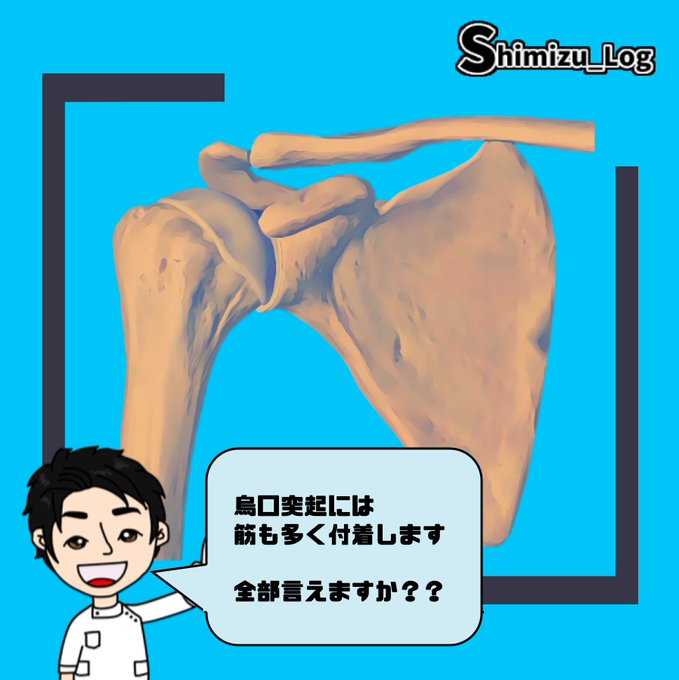

今日は烏口突起に付着する"筋"を学んでいきましょう!

"内側から外側"

にどのような順で筋が付着するか?

そして

外側は"表層・深層"

にどういった位置関係で筋が付着するか?

3次元で考える必要があります^_^

特に

上腕二頭筋短頭と烏口腕筋は

臨床でも重要だと思います😁